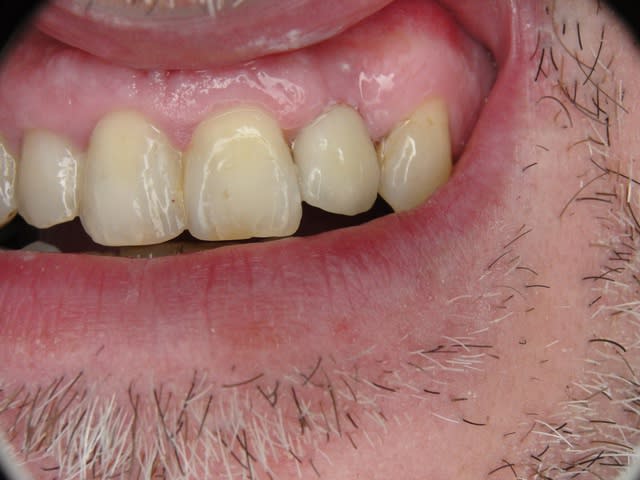

Merci pour le cas, bien fait. Belle présentation photo.

Le contour gingival est net, belle guérison, c'est à combien de semaine ?

Je vois un peu de ciment sur la radio finale, attention, c'est pas bien pour les tissus.

La pose de la couron nec'est faite 8 semaines apres l'extraction implantation immédiate, la particularité de ce systeme permet de ne pas démonter le shuttle ni la gingivaclip pour l'empreinte..je pense que ca aide bien à la qualité gingivale...radio controle ci jointe